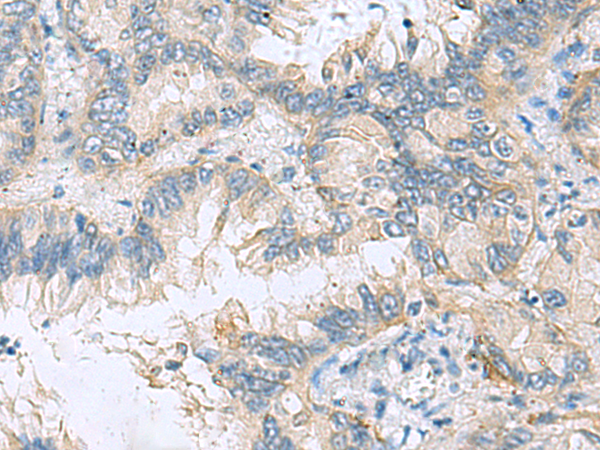

分类: 科研抗体货号: P10303别名: DS1; DS-1; ICT1; MRP-L58应用: IHC反应种属: Human, Mouse